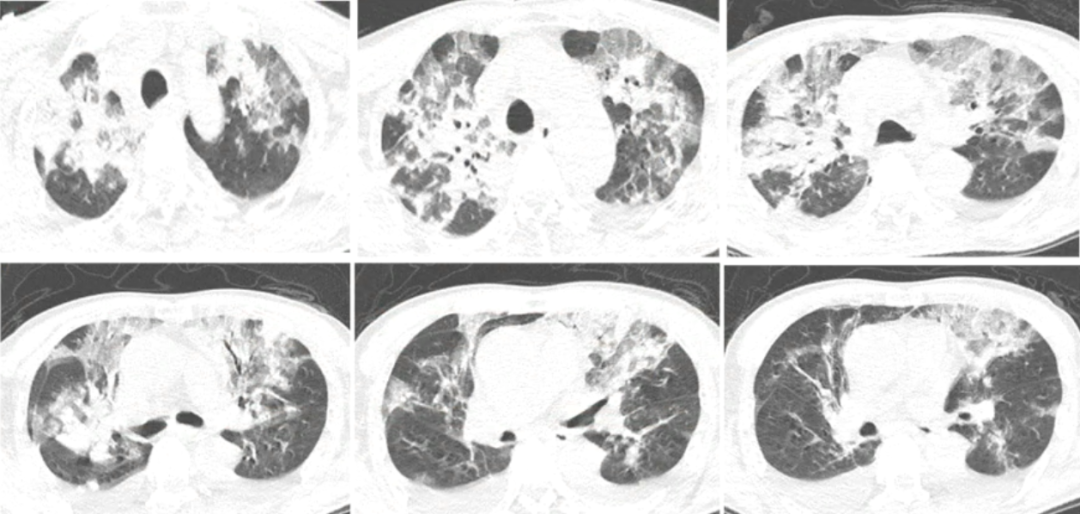

2020年12月12日,复查胸部CT:双上肺磨玻璃影明显增多,下肺重力依赖区依然存在实变影,少量胸腔积液(图3)。

图3 患者胸部CT(2020-12-12)

复查胸部CT(2020-12-16):双上肺病变仍然较重,双下肺重力依赖区实变影明显吸收,双侧少量胸腔积液(图5)。

图5 患者胸部CT(2020-12-16)

2020年12月23日复查胸部CT:双上肺病变明显吸收,遗留少量斑片条索影,双下肺吸收良好(图7)。

图7 患者胸部CT(2020-12-23)